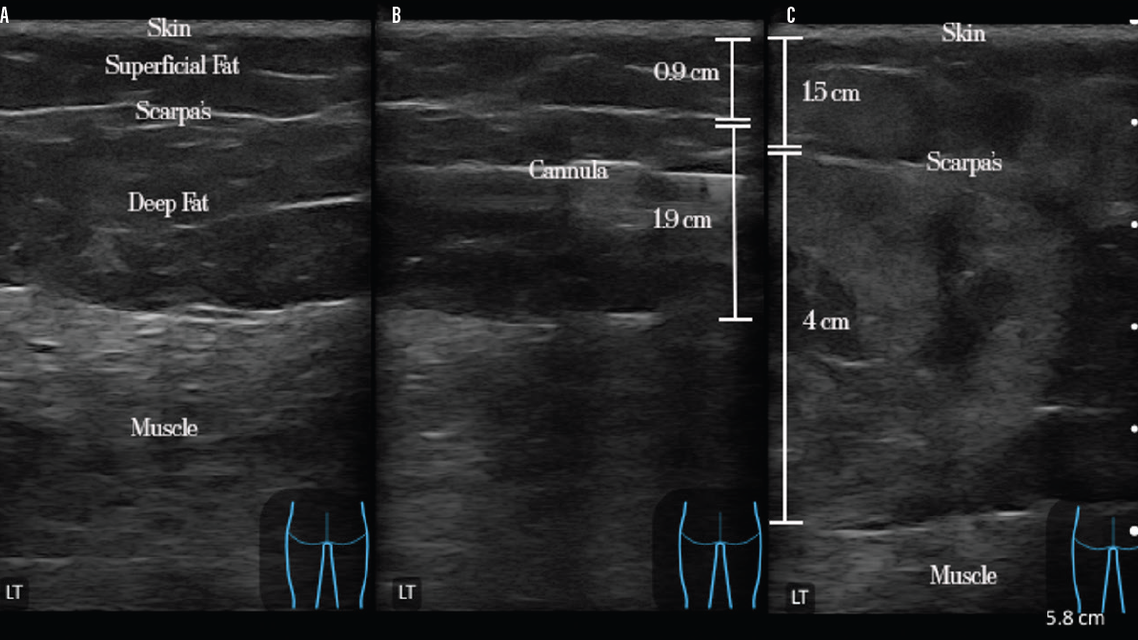

“ULTRA” BBL or Ultrasound-guided Lipofilling Targeting Recipient Areas could be a solution to the problem.25 As described by Dr. Pat Pazmiño, this method uses ultrasound to identify the superficial and deep fat layers and the muscle (Figure 1A). It leverages subcutaneous fat migration concepts targeting fat to the deep subcutaneous layer in a static fashion. Once the cannula is corroborated to be in the deep subcutaneous layer (Figure 1B), fat is infiltrated without moving the cannula. The benefits of this technique include shorter ultrasound times, smaller volumes of fat required to achieve an overall aesthetic result, accurate graft placement, and certainty that the fat has been placed in the correct plane(s) (Figure 1C). In Figure 1C, observe the expansion achieved in the deep subcutaneous layer versus the superficial subcutaneous layer, which has more septae.

Figure 1. A. Identification of layers of the buttock using ultrasound. B. Visualization of the fat grafting cannula in the deep subcutaneous space with measurements of the superficial and deep fat layers prior to fat injection. C. Measurement of the fat layers after ULTRA BBL fat transfer.